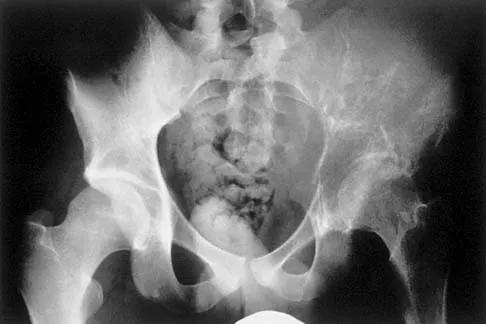

Figure 17 shows the AP radiograph of a 5-year old child who has mild short stature and a painless bilateral gluteus medius lurch. Initial work-up should include

Detailed Explanation

Bilateral flattening of the femoral heads suggests multiple epiphyseal dysplasia; therefore, a skeletal survey is indicated to look for involvement of other epiphyses. Unilateral flattening of the femoral head would suggest Legg-Perthes disease. Sponseller PD: Skeletal dysplasias, in Morrissy RT, Weinstein SL (eds): Lovell and Winter's Pediatric Orthopaedics, ed 5. Philadelphia, PA, Lippincott Williams & Wilkins, 2001, pp 269-270.